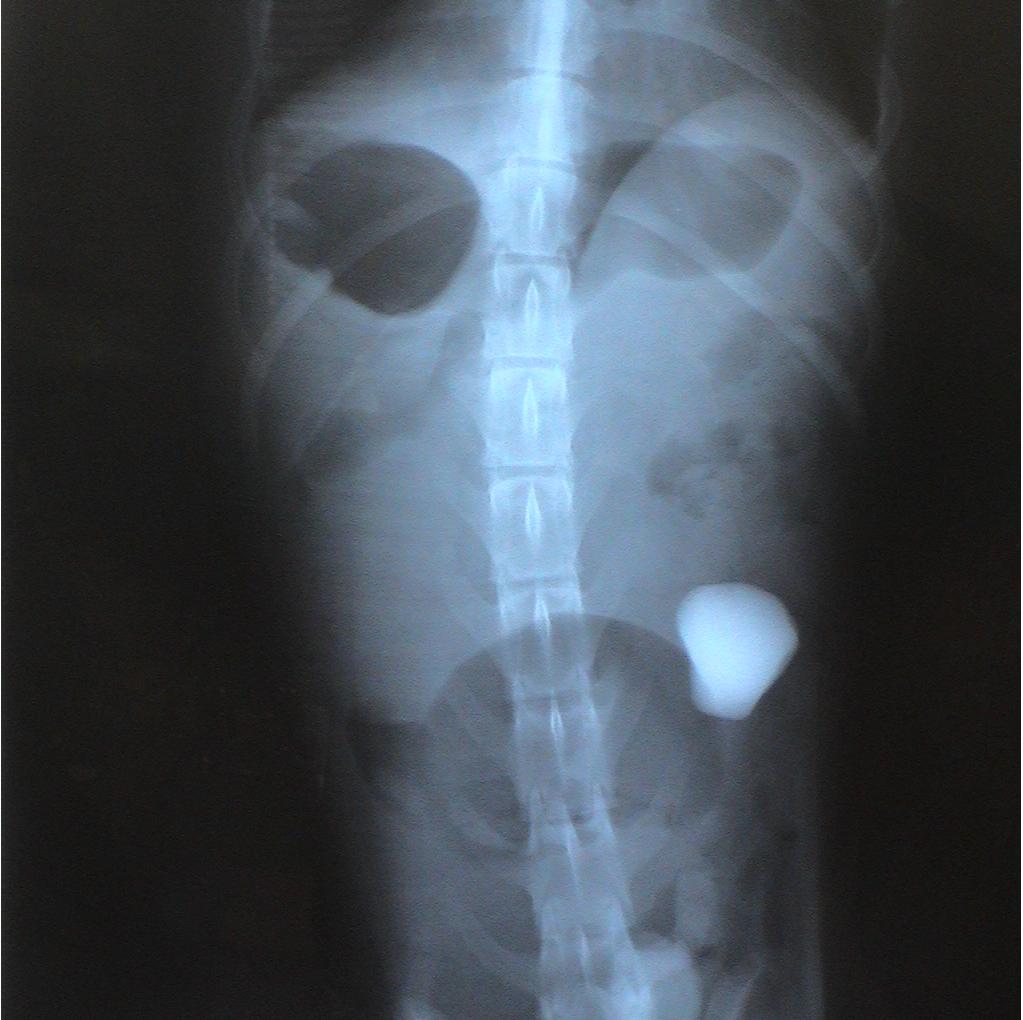

Two sets of radiographs are always taken to localize lesions and identify problems. Radiographs are flat pictures of three-dimensional animals! If one view is taken, things can be lost as structures will overlap each other. For example, the rock is located on the left side of the abdomen which is clearly evident on the second set of radiographs. This is not evident in the first set since the left and right sides of the dog overlap each other.

Notice the difference in the shape of the circled structures depending on the position of the animal.